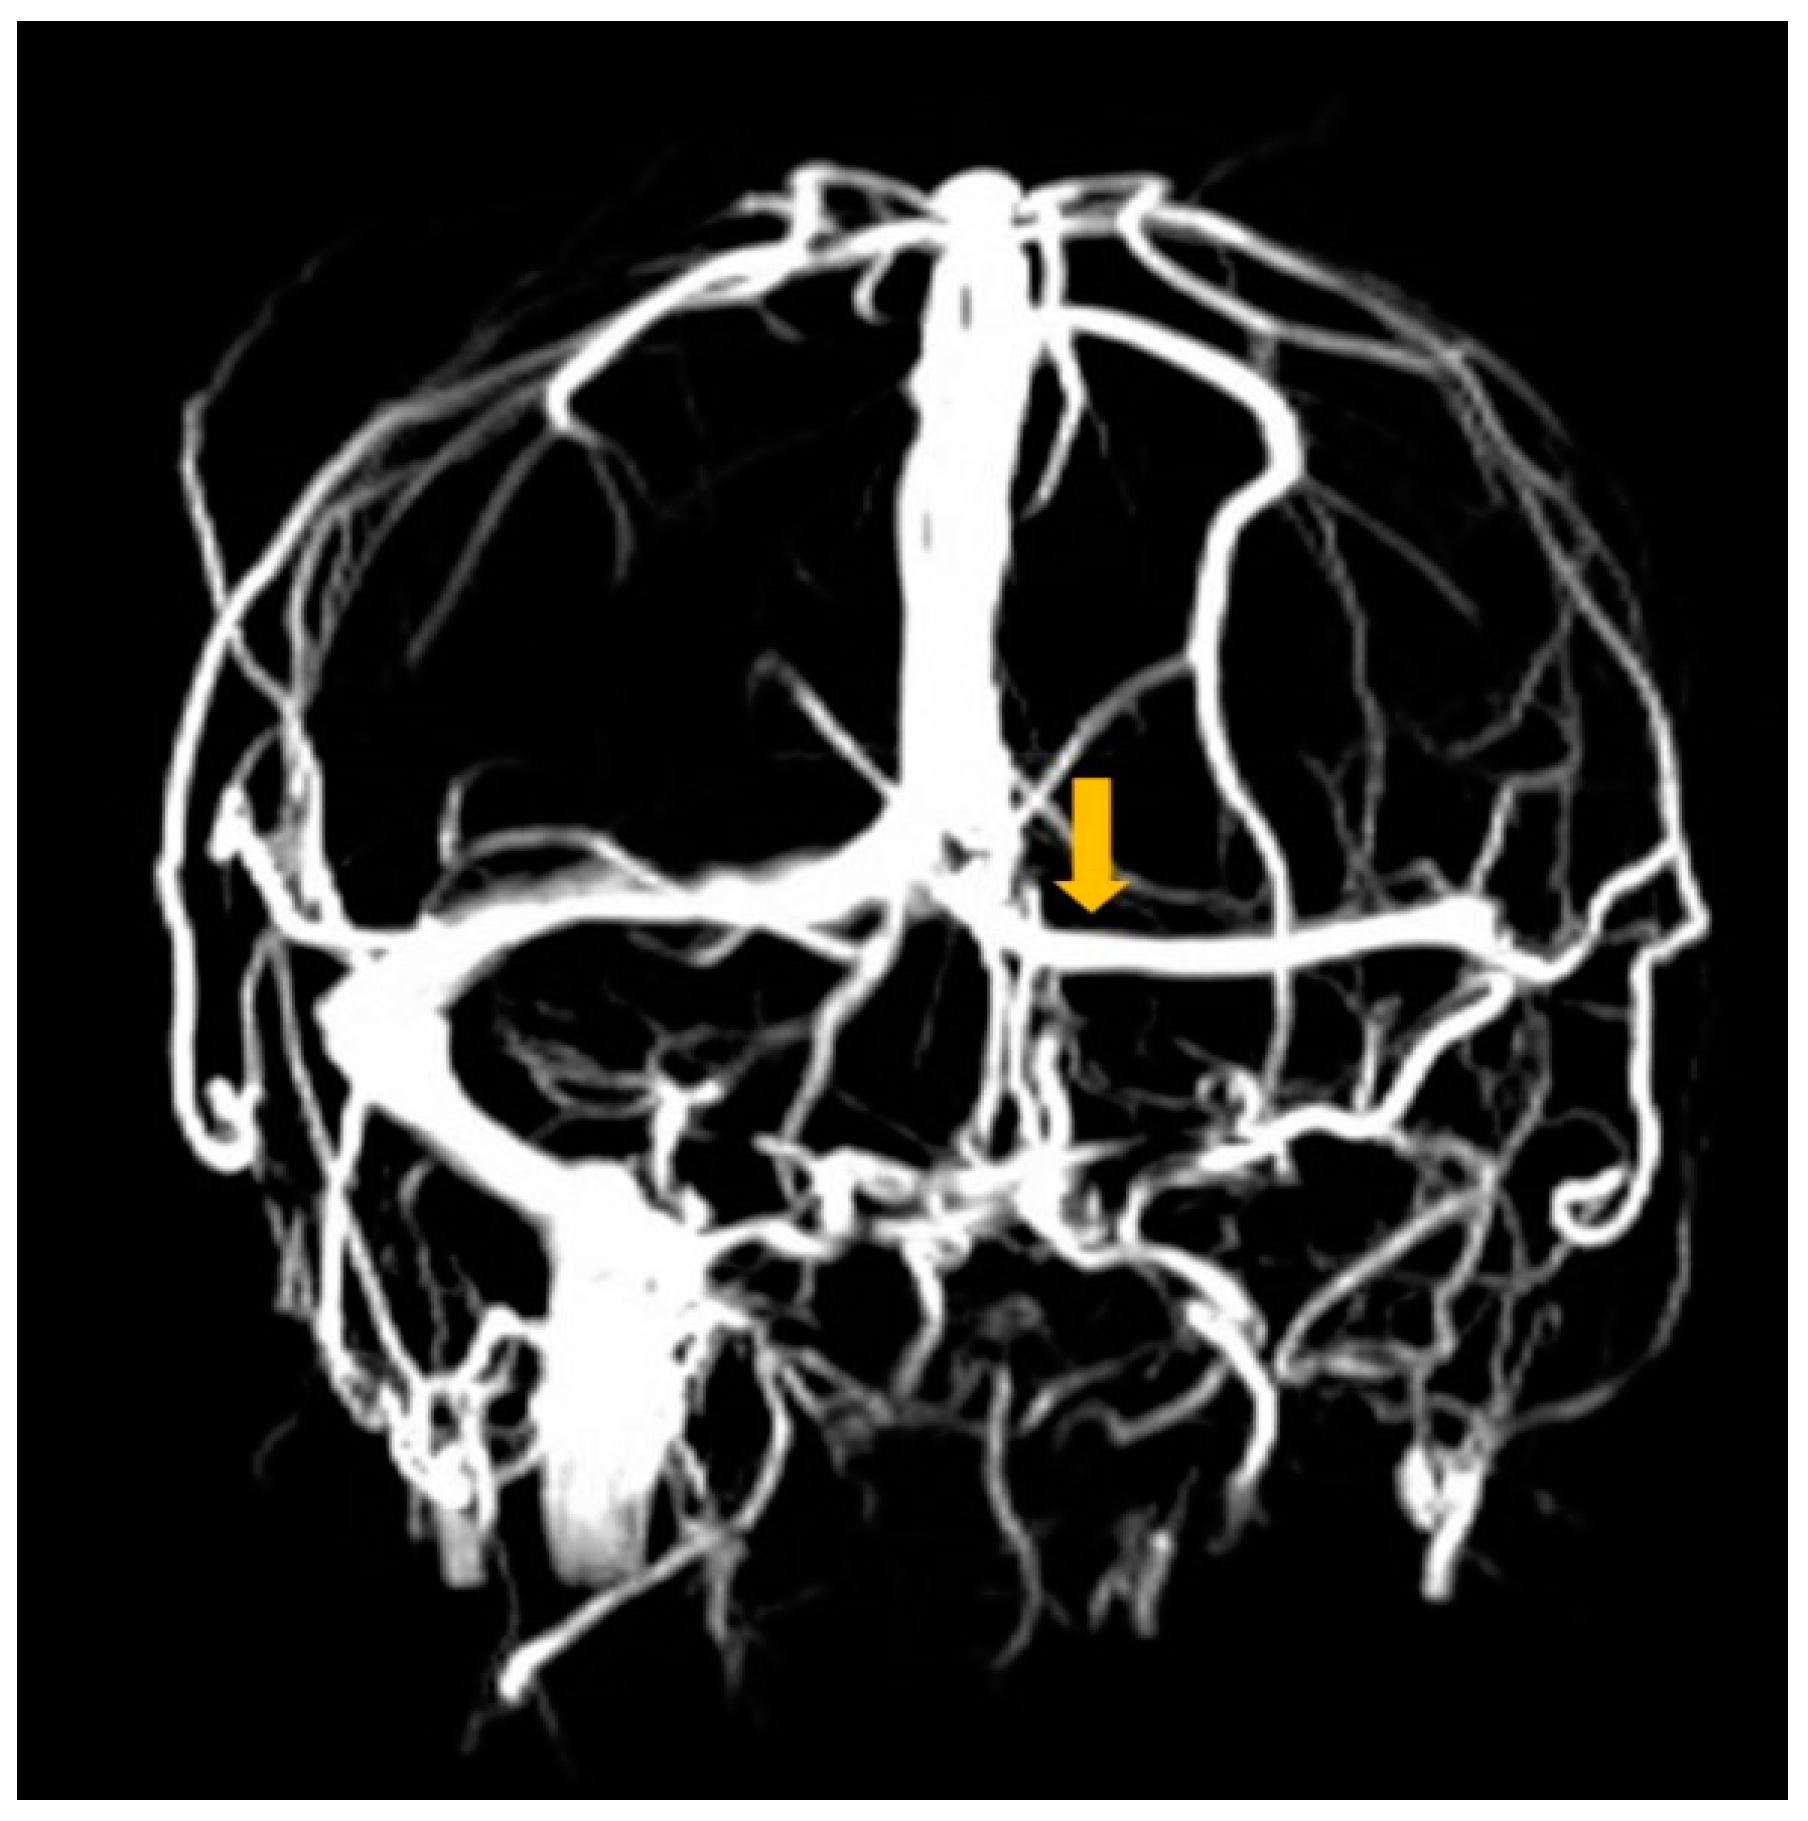

2. Case Report